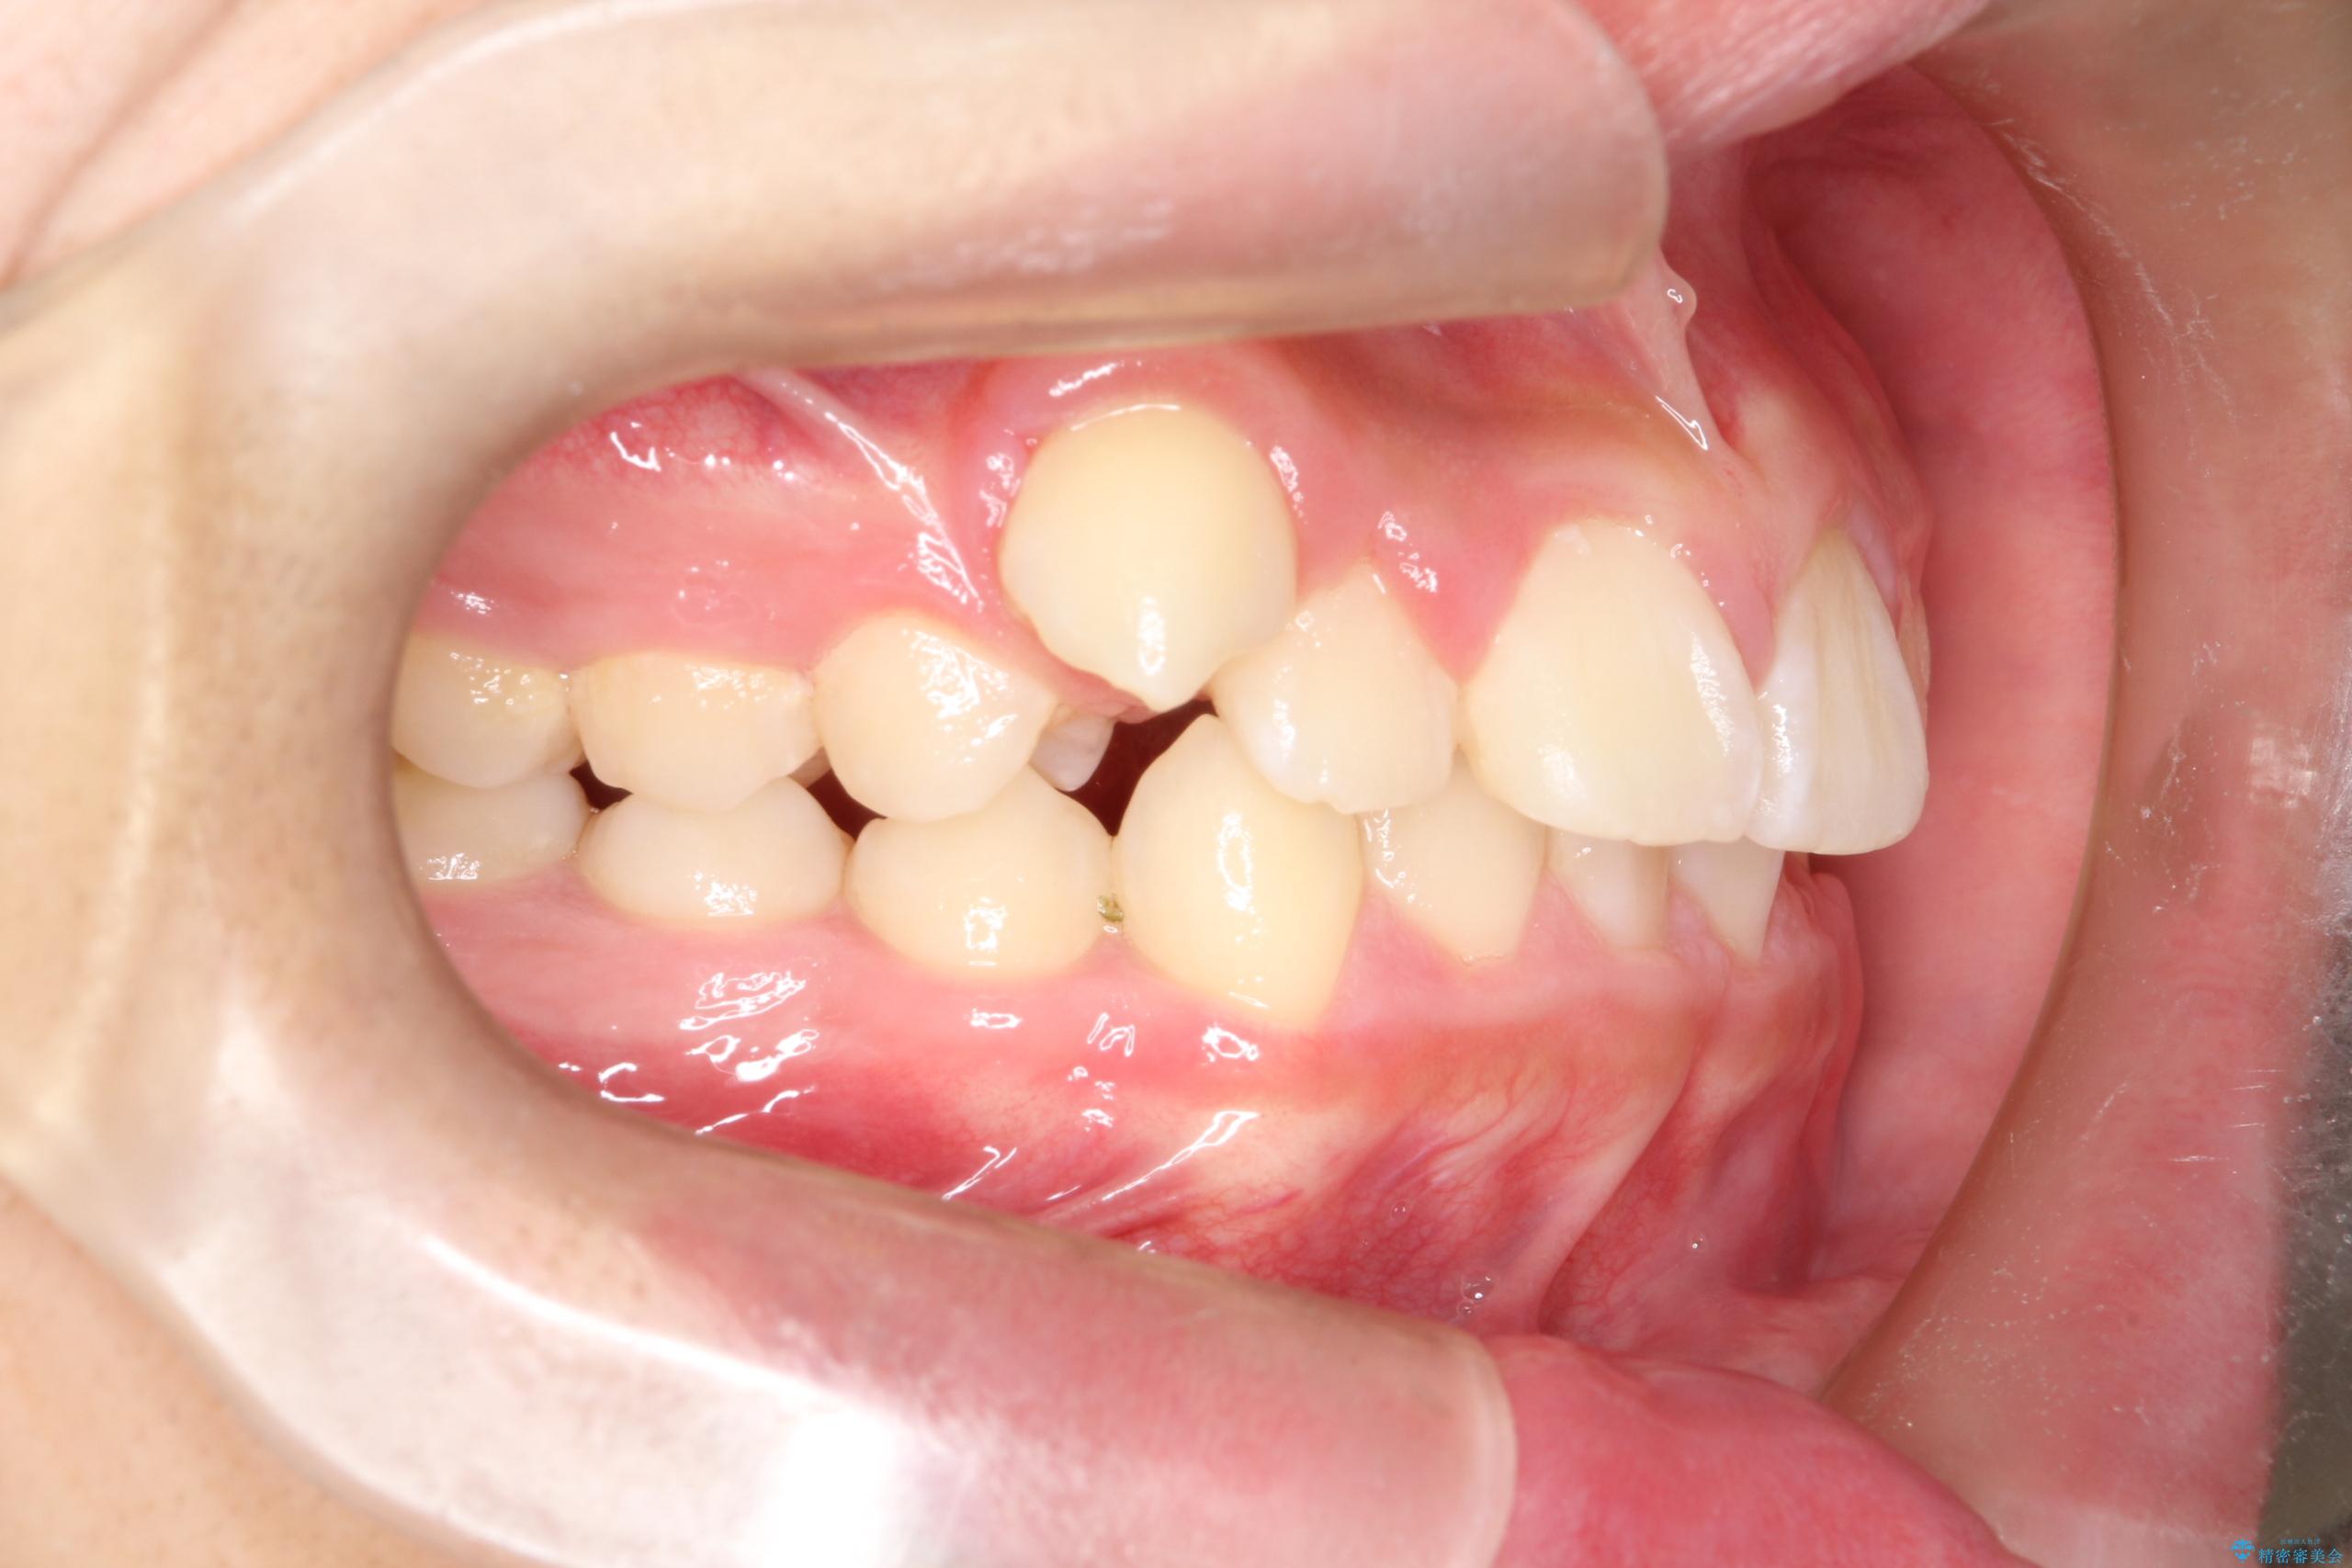

八重歯・歯並びのデコボコとディープバイトを改善した抜歯ワイヤー矯正症例

- 八重歯と咬み合わせを治したいを主訴にご来院された患者様です。

矯正の精密検査の結果上顎左右4番の計2本を抜歯し、審美性に配慮したワイヤー矯正装置(審美装置)を用いて治療を行いました。

八重歯などの歯列のデコボコが綺麗に改善され、患者様にも大変喜んでいただけました。また、咬み合わせが深い「ディープバイト」も併せて改善し、見た目だけでなく機能面でもバランスの取れた咬合を獲得しています。